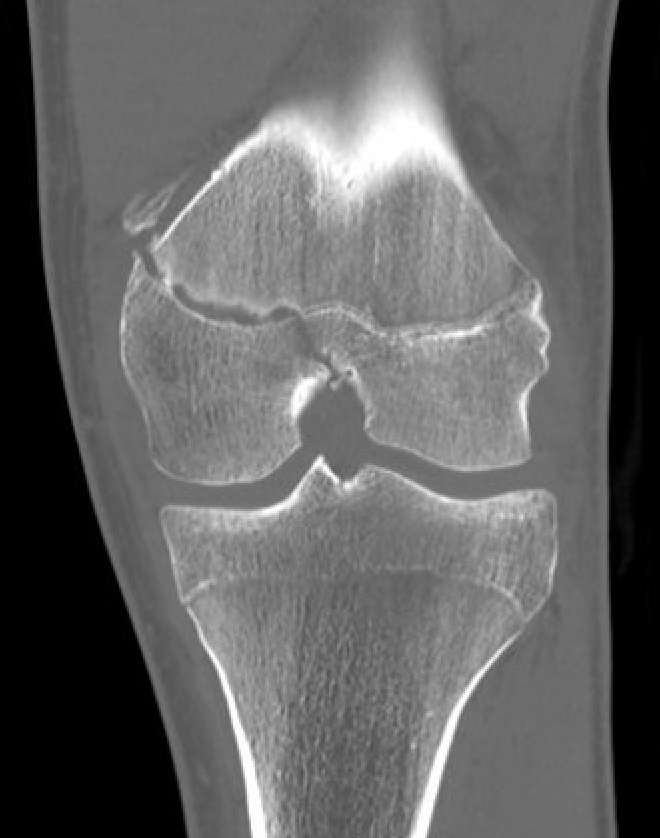

Partial growth arrest / angular deformity

SH2Dis femurDis femur

Management

CT / MRI - assess percentage of bony bridge

Bony bridge < 50%

- excision and fat graft

- manage angular deformity with 8 plates / osteotomy

Bony bridge > 50%

- hemi-epiphysiodesis

- may need later correction of LLD and angular deformity